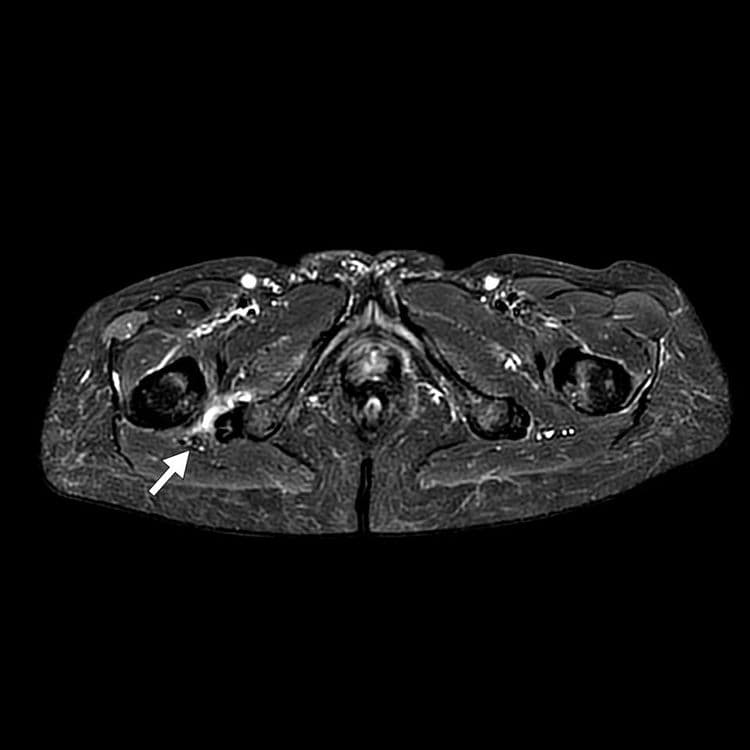

Conflit par réduction de l’espace entre le rebord ischiatique et la tête fémoral

MRI